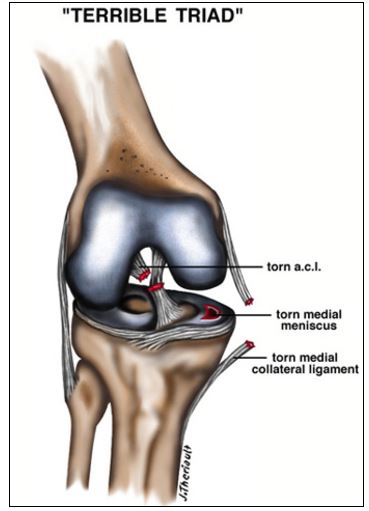

ACL rupture is often associated with meniscal and medial ligament injury. This combination is known as a the “terrible triad” of knee injuries.

In order to preserve the precious chondral surfaces of the knee, and prevent arthritis later in life, these injuries must be repaired. The ACL must be reconstructed, the medial ligament can be repaired, or rested to allow healing, and the meniscus can be surgically repaired. Depending on the extent of the injuries a patient may or may not be placed in a knee brace after surgery to protect the repairs.

Injuries associated with ACL rupture often dictate the outcome the reconstruction surgery. Knees with meniscal involvement often have a poorer outcome.

If the ACL is left unreconstructed and the knee develops recurrent instability the meniscus can rupture with subsequent episodes of instability as well. So if you have symptoms of recurrent instability after knee injury do not ignore it- seek expert medical opinion.